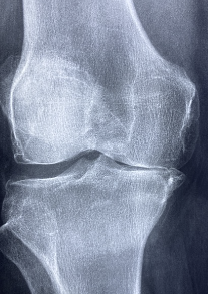

4. 관절염: 관절염은 관절에 염증이 생기는 질환을 말합니다. 관절염에는 여러 종류가 있지만, 가장 흔한 것은 골관절염과 류마티스 관절염입니다. 골관절염은 나이가 들면서 연골이 닳아서 발생하는 질환으로, 주로 50세 이상의 사람들에게 많이 나타납니다. 류마티스 관절염은 면역 체계가 잘못 작동하여 자신의 조직을 공격하는 자가면역 질환으로, 주로 40세 이하의 여성에게 많이 나타납니다. 관절염이 발생하면 무릎 관절에 통증, 부기, 열감, 강직감 등의 증상이 나타날 수 있습니다.

무릎 관절 원인

무릎 관절의 원인은 다양합니다. 가장 흔한 원인은 연령에 따른 자연적인 퇴행입니다. 나이가 들면서 연골이 닳아가고 관절의 윤활액이 감소하면서 무릎 관절에 마찰이 발생하고 통증이 생깁니다. 이를 노화성 관절염이라고 합니다. 노화성 관절염은 만성적이고 진행적인 질환으로 완치하기 어렵습니다. 하지만 적절한 치료와 운동으로 증상을 완화하고 진행을 늦출 수 있습니다.